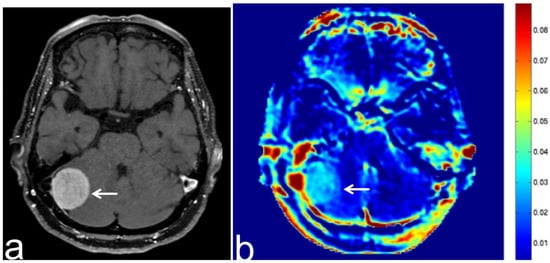

6. APT-CEST Imaging of Meningioma